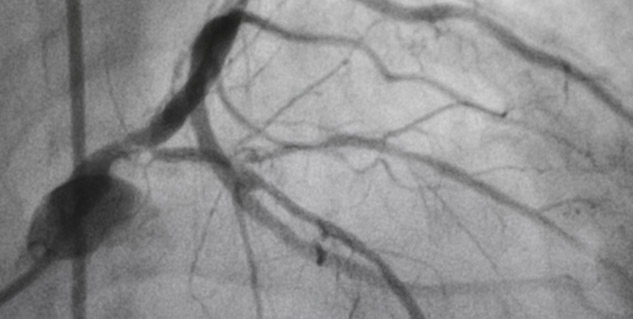

डॉक्टर बताते हैं कि हाथ या फिर जांघ के जरिए कैथेडर को शरीर में डालते हैं। कैथेडर बारीक की पाइप होती है। जो हमारे नस के जरिए डाला जाता है और धीरे-धीरे हार्ट की नसों तक पहुंचा दिया जाता है। डॉक्टर इसे मशीन के बाहर लगे मॉनिटर सिस्टम पर देखते हुए करते हैं। ताकि किसी प्रकार की दिक्कत न हो। कैथेडर में खास प्रकार की डाई होती है, जब कैथेडर हार्ट में कोरोनरी आर्टरी में पहुंच जाता है, डाई के जरिए अंदर की तस्वीर को डॉक्टर आसानी से देख पाते हैं, जिससे ब्लॉकेज का आसानी से पता लगाया जाता है।

एक्सरे इमेजनरिंग भी है खास तकनीक, एंजिओग्राम है रिपोर्ट का नाम

डॉक्टर बताते हैं कि इस तकनीक के जरिए आर्टरी और वींस के अंदरुनी भाग को डॉक्टर जांच करते हैं। कहां ब्लॉकेज है या नहीं पता करते हैं। डॉक्टर इसी एक्स-रे इमेजनरिंग के जरिए रिपोर्ट तैयार करते हैं। जिसे एंजिओग्राम (Angiogram) कहा जाता है। एक बार ब्लॉकेज का पता चल जाए तो डॉक्टर मरीज को एंजियोप्लास्टी कराने की सलाह देते हैं।